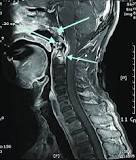

Neck pain with weakness in the arms and tingling in the fingers may indicate a herniated disc, which is pressure on a nerve root due to a narrowing of the spinal cord canal. Call our office immediately.

Cervical whiplash injuries result in the cranial cervical syndrome (CCS); a complex of symptoms which include disabling intractable migraine headaches, neck pain, radiculomyelopathies, concentration and memory problems, visual disturbances, ataxia, nausea, autonomic disturbances and chronic pain. Utilizing new analytic modalities, including digital motion X-ray and upright positional MRI, correlated with clinical findings, we were able to clearly define the syndrome in 39 patients. C1-C2 transarticular fixation/fusion and suboccipital craniectomy resulted in near total resolution of the disabling headaches and associated symptoms. We hypothesize that lateral C1-C2 instability-induced transient vertebral artery compression explains the CCS, and that fixation resolves the syndrome.